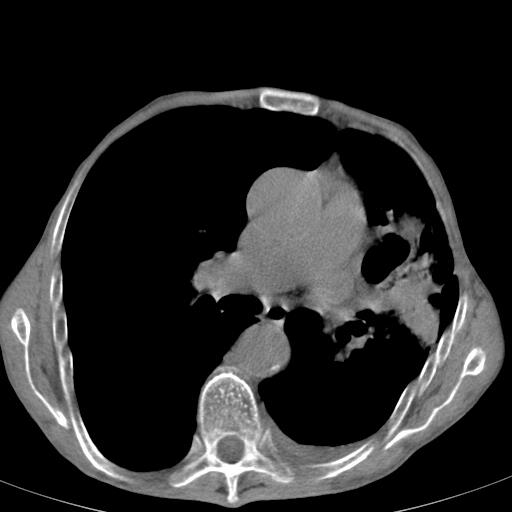

患者78岁,咳嗽胸闷一年余,近月来左侧胸痛;

建议强化,首先考虑左肺癌胸膜转移。

左侧少量胸腔积液,局限胸膜增厚,结合病史,考虑慢性肺炎.

患者左侧胸廓塌陷说明是长期病变,考虑tb性胸膜炎可能性大,另外有明显的肺气肿,建议行结核菌素实验,或者增强扫描

1.慢支肺气肿。2.左肺感染,建议治疗后复查。3.左侧少量胸水。

1.慢支肺气肿。2.左肺感染,建议治疗后复查,待除外继发性肺结核合并感染。3.左侧少量胸水。

1)考虑左肺慢性感染性病变(结核可能)。2)左肺上叶周围型肺癌不排除;建议追踪复查。3)肺气肿。4)左侧胸腔积液,左侧胸膜增厚、粘连。